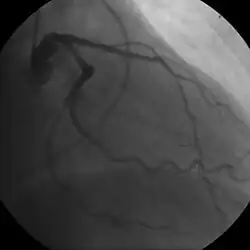

Coronary angiogram of a male

Coronary angiogram of a female

The diagnosis of CAD depends largely on the nature of the symptoms and imaging. The first investigation when CAD is suspected is an electrocardiogram (ECG/EKG), both for stable angina and acute coronary syndrome. An X-ray of the chest, blood tests, and resting echocardiography may be performed.[73][74]

For stable symptomatic patients, several non-invasive tests can diagnose CAD depending on pre-assessment of the risk profile. Noninvasive imaging options include; Computed tomography angiography (CTA) (anatomical imaging, best test in patients with low-risk profile to "rule out" the disease), positron emission tomography (PET), single-photon emission computed tomography (SPECT)/nuclear stress test/myocardial scintigraphy and stress echocardiography (the three latter can be summarized as functional noninvasive methods and are typically better to "rule in"). Exercise ECG or stress test is inferior to non-invasive imaging methods due to the risk of false-negative and false-positive test results. The use of non-invasive imaging is not recommended on individuals who are exhibiting no symptoms and are otherwise at low risk for developing coronary disease.[75][76] Invasive testing with coronary angiography (ICA) can be used when non-invasive testing is inconclusive or show a high event risk.[74]